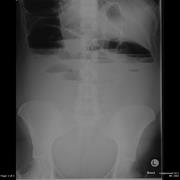

A rare cause of bowel obstruction in pregnancy

Yingda Li and others

Journal of Surgical Case Reports, Volume 2012, Issue 12, December 2012, rjs034, https://doi.org/10.1093/jscr/rjs034